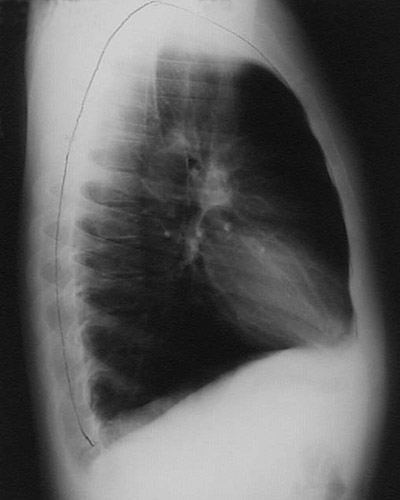

The chest radiograph in lateral view seen here demonstrates a marked increase in size of the chest cavity from emphysema. There is increased lucency due to the loss of lung parenchyma from emphysema